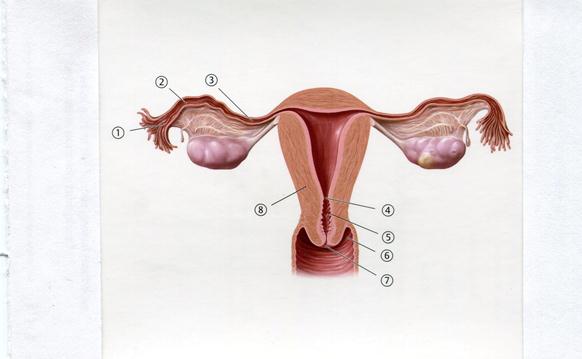

64. Төменде көрсетілген суреттегі белгіленген № 5 анатомиялық құрылымды атаңыз.

А.Ампуласы

В.Жатыр түтігінің қылтасы

С.Жатыр тесігі

+D.Мойын өзегі

Е.Шашақтары

66. Төменде көрсетілген суреттегі белгіленген №5 анатомиялық құрылымды атаңыз.

А.Жатыр

В.Қасаға симфизі

С.Қынап

+D.Несеп қуық

Е.Тік ішек